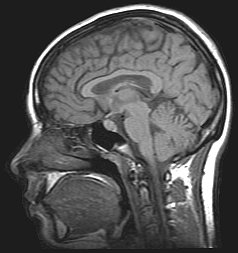

Cognitive neuroscience aims to reduce cognition to its neural basis using new technologies such as fMRI, repetitive transcranial magnetic stimulation (rTMS) and Magnetoencephalography (MEG) as well as older methods such as Positron emission tomography (PET) and Electroencephalography (EEG) studies. Due to the correlational designs used in fMRI, many scientists have coined this up and coming field as the new phrenology in the sense that techniques such as fMRI rely heavily on complex statistics.[17] Type 1 errors can lead scientists to draw premature and incorrect causal relationships if improper designs are used.[18]

Functional magnetic resonance imaging (fMRI) has intriguing implications for the study of memory in humans, however it can also be used in animal models. fMRI can be used to assess brain functionality in monkeys in the context of a variety of behavioral tasks.[26] Structural MRI can be used to examine the extent and location of brain lesions, so that behavioral abnormalities observed can be directly linked to specific brain structures.[27] High-resolution fMRI can help locate and assess the functionality of large neural networks so that these regions can be further studied using more traditional electrophysiological recording devices.[26]